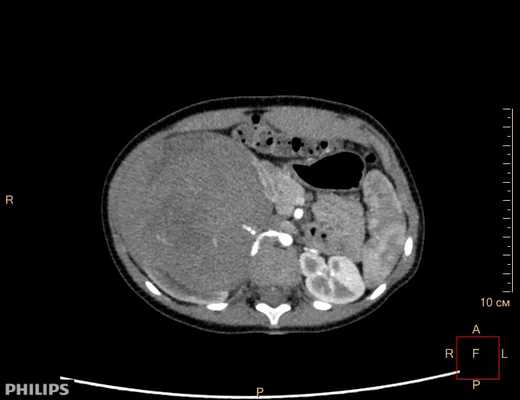

3D-реконструкции опухоли Вильмса пациентов детского отделения НМИЦ онкологии им. Н.Н. Петрова

Опухоль Вильмса. Компьютерная томография